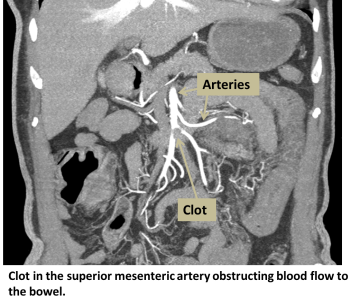

Clot in the superior mesenteric artery obstructing blood flow to bowel

The blood supply to the gastrointestinal tract comes from three branches of the aorta: the celiac artery, the superior mesenteric artery, and the inferior mesenteric artery. Because there is overlap between the areas that these arteries supply, the arteries can try to compensate for blockages in other areas. However, uncompensated areas will suffer more damage from decreased blood flow.